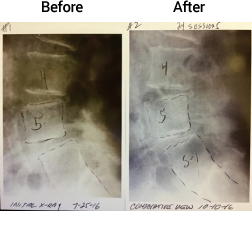

전방전위증

미국인